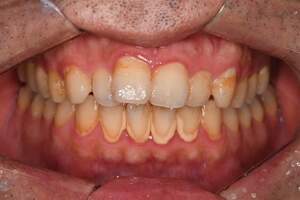

PMTC・オフィスホワイトニング

治療前

治療後

| 年齢 | 46歳・男性 |

|---|---|

| 主訴 | 着色を取りたい・歯を白くしたい |

| 治療内容 | PMTC・オフィスホワイトニング |

| 治療期間 | 90分 |

| 費用 | PMTC 5,500円 オフィスホワイトニング2回 6,600円(自費 診療) |

| リスク・副作用 | ・生活習慣(喫煙・コーヒーなど)により再度着色することがあります ・詰め物や被せ物はホワイトニングでは白くなりません ・ホワイトニングの効果は永久的なものではなく徐々に色戻りが起こります ・ホワイトニング後は歯の表面の水分量が一時的に少なくなりしみることがあります ・保険適用外の施術です |